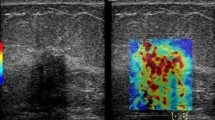

The mass was located in the center of the elasticity boxes on a plane showing the longest diameter, and SWE images were obtained without compression. The elasticity boxes included the mass and surrounding tissues. The US transducer was held over the mass for a few seconds to stabilize the SWE image before the image was saved for SWE measurements. The elasticity color map was overlaid on the B-mode image; the softest parts were displayed in blue and the hardest parts in red. Quantitative elasticity parameters were measured on the elasticity color map image using the US system’s built-in quantification tool. The default quantitative scale ranged from 0 to 200 kPa. Two round 2-mm-diameter regions of interests were positioned on the hardest part of the mass and adjacent adipose tissue.

The US system automatically displayed the SWE parameters such as average elasticity of the tumor (Eaverage) with standard deviation, average elasticity of the adjacent fat with standard deviation, and elasticity ratio between the tumor’s average elasticity and the average elasticity of adjacent fat (Eratio) (Fig. 2a). We extracted the two quantitative SWE parameters Eaverage and Eratio, and used these to examine the relationships between stiffness parameters on SWE and immunohistochemical staining for intratumoral hypoxia in breast cancers. In our hospital, we repeated the SWE examination three times for each suspicious breast mass and measured Eaverage and Eratio values three times for each mass. We used the mean of the three measurements of Eaverage and Eratio for statistical analysis.

Quantitative measurement of tumor stiffness on shear-wave elastography (SWE) and immunohistochemical staining. a. Quantitative elasticity parameters were measured on the elasticity color map image. Two round 2-mm-diameter regions of interests were positioned on the hardest part of the mass and adjacent adipose tissue. The ultrasound system automatically displayed average elasticity of the tumor (Eaverage) with standard deviation, average elasticity of the adjacent fat with standard deviation, and elasticity ratio between the tumor’s average elasticity and the average elasticity of adjacent fat (Eratio). Two quantitative SWE parameters, Eaverage (yellow box) and Eratio (green box), were extracted to investigate the relationships between stiffness parameters on SWE and immunohistochemical staining. b–c. On immunohistochemical staining, the area fraction of positive reactions was measured. Each color image was converted to a binary image. The positive areas—brown area for glucose transporter-1 protein (GLUT1) staining (× 100) (b)—were converted to red (c). The area fraction of positive GLUT1 reaction was determined as the percentage of red pixels in the binary image